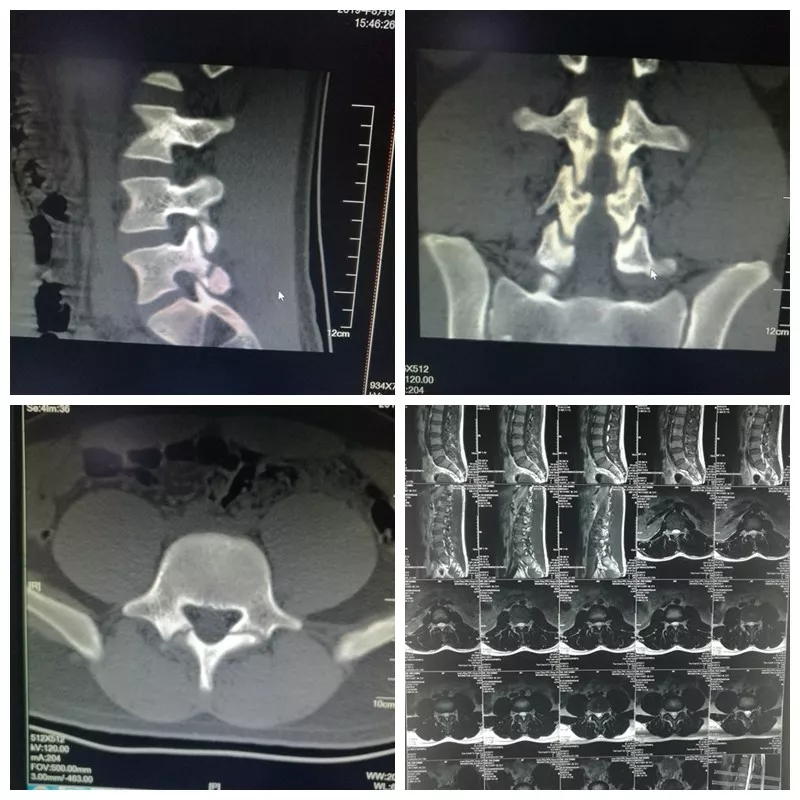

日前,西甲网上买球网站脊柱科成功开展唐山市首例椎扳钩修补腰椎峡部裂结合自体骼骨植骨融合技术。此手术采用国内领先的椎板钩固定,自体骼骨植骨融合技术,对单纯青年人腰椎峡部裂慢性腰痛患者,方法可靠,治疗效果显著。该手术主要适应年轻而又对术后活动要求较高的患者,具有安全性高、创伤小、手术时间短、操作简单、术后恢复快等优点。该患者为男性,19岁,自幼学习舞蹈。术前患者腰骶部疼痛10余年,疼痛加重、影响活动半年。

术后患者下腰痛症状基本消失,活动度明显改善。重建CT示:峡部裂已融合。